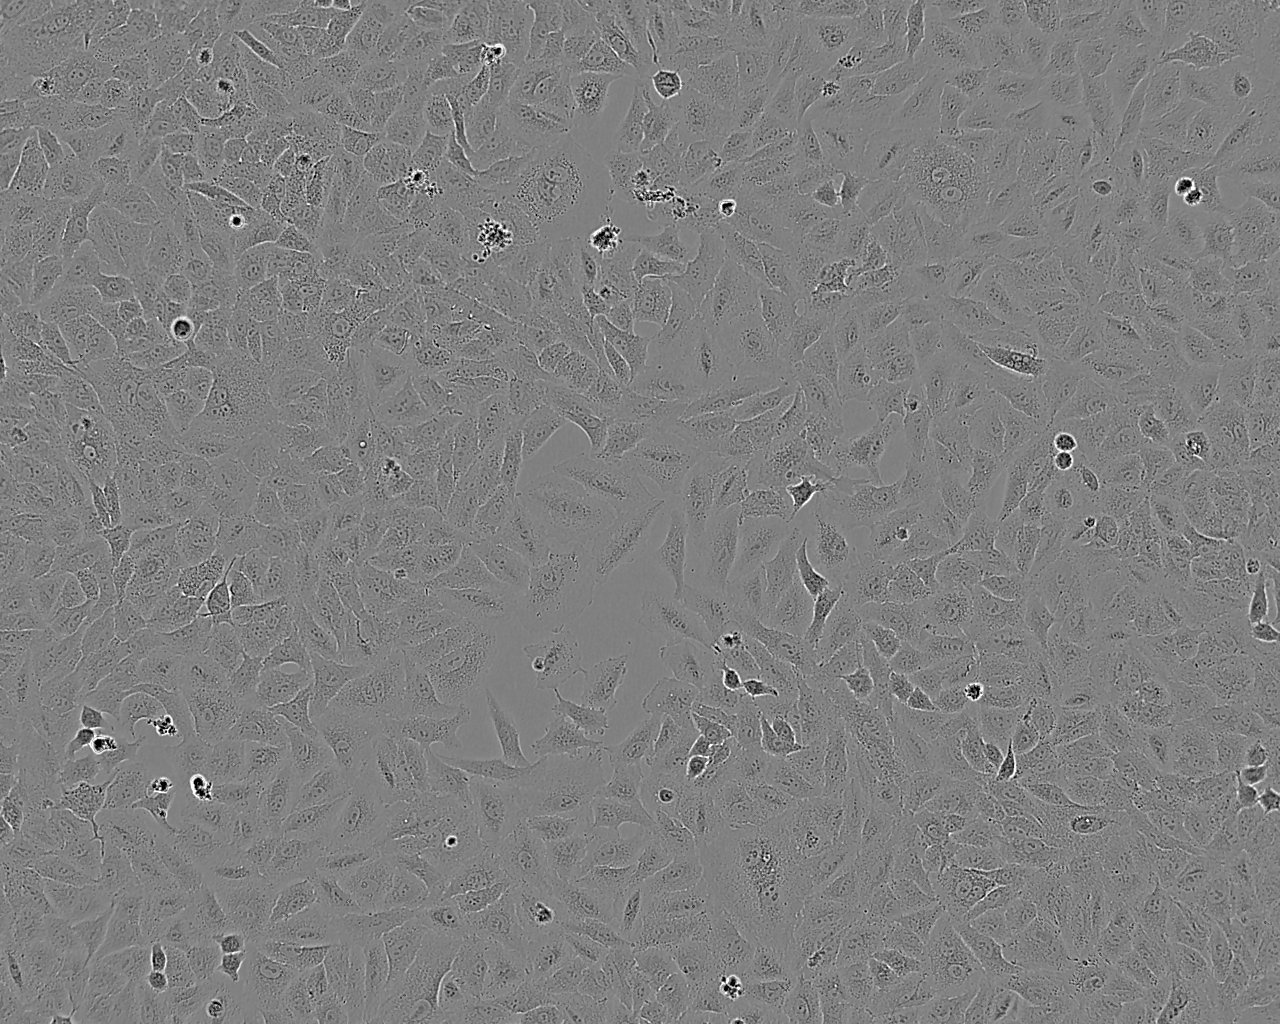

细胞形态:上皮细胞样

细胞生长:贴壁

细胞背景资料:该细胞1982年建系,源自非小细胞肺癌男性患者的转移淋巴结。

细胞形态特性:圆形细胞

细胞生长特性:悬浮生长